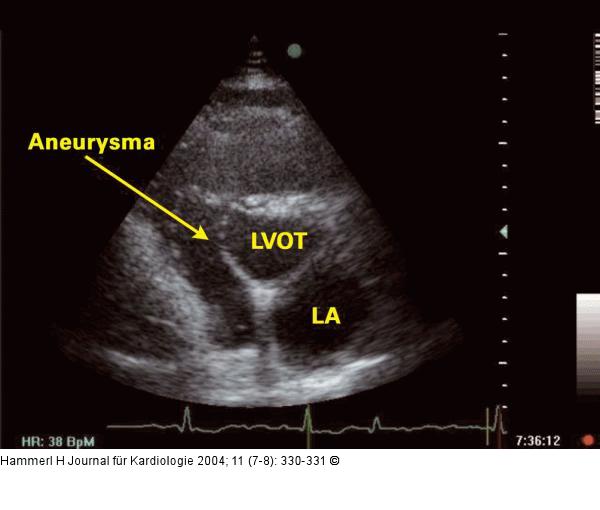

Abbildung 2: Interventrikuläres Septum - Aneurysma Parasternaler Querschnitt auf der Ebene des linksventrikulären Ausflußtraktes: Aneurysma des interventrikulären Septums; LA = linker Vorhof; LVOT = linksventrikulärer Ausflußtrakt |

Abbildung 2: Interventrikuläres Septum - Aneurysma

Parasternaler Querschnitt auf der Ebene des linksventrikulären Ausflußtraktes: Aneurysma des interventrikulären Septums; LA = linker Vorhof; LVOT = linksventrikulärer Ausflußtrakt |